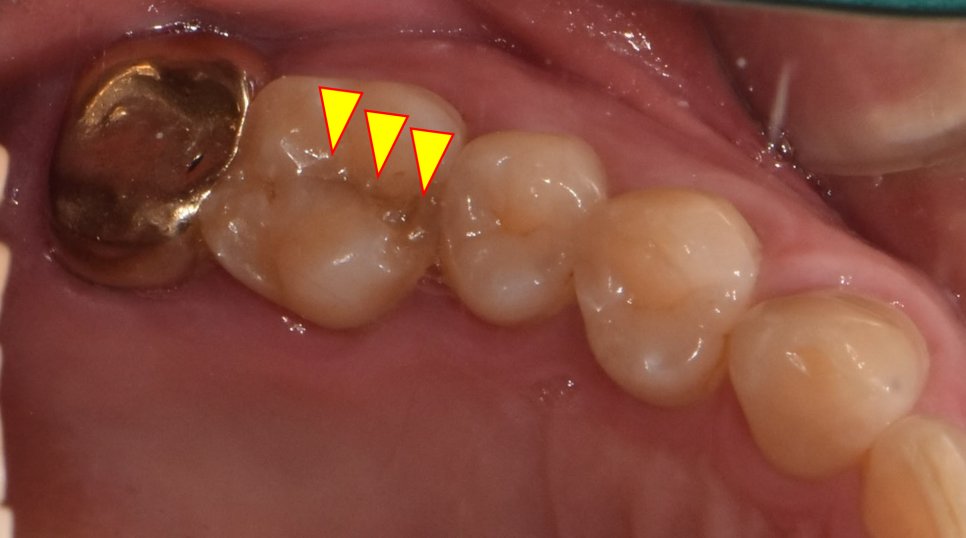

23.12.29(초진) – 53y 이OO님

조금더 크게 확대해서 보도록 하겠습니다.

노랑색화살표가 가리키는 선이 보이시나요?

네, 맞습니다.

어금니깨짐이 발생한 치아 입니다.

말도 많고 탈도 많은 크랙치아..

(Crack tooth syndrome)